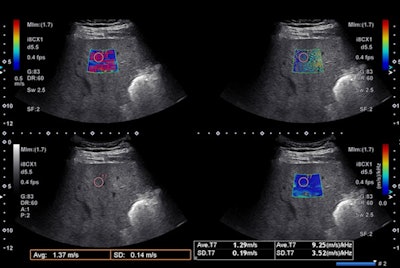

For most effective use of SWE, the ultrasound transducer should be positioned in an intercostal space -- perpendicular to the liver in both superior/inferior and right/left planes. The transducer's position can be assessed by looking at the liver capsule that appears as a sharp white line, parallel to the transducer's line, the authors said.

Also, be sure to avoid the ribs or the lung artifacts and note the quality of the B-mode image affects the quality of the SWE acquisitions. Common limitations such as poor acoustic window, limited penetration, and rib or lung shadowing can influence the feasibility and the performance of SWE. However, some of these limitations can be avoided.

Patients should breathe normally while the sonographer is searching for the best acoustic window and best area of liver parenchyma. However, before acquiring the SWE image, the sonographer should ask the patient to hold their breath in a neutral position without performing a Valsalva's maneuver. Measurements should be performed at least 1-2 cm below the liver capsule to avoid reverberation artifacts, the authors added.